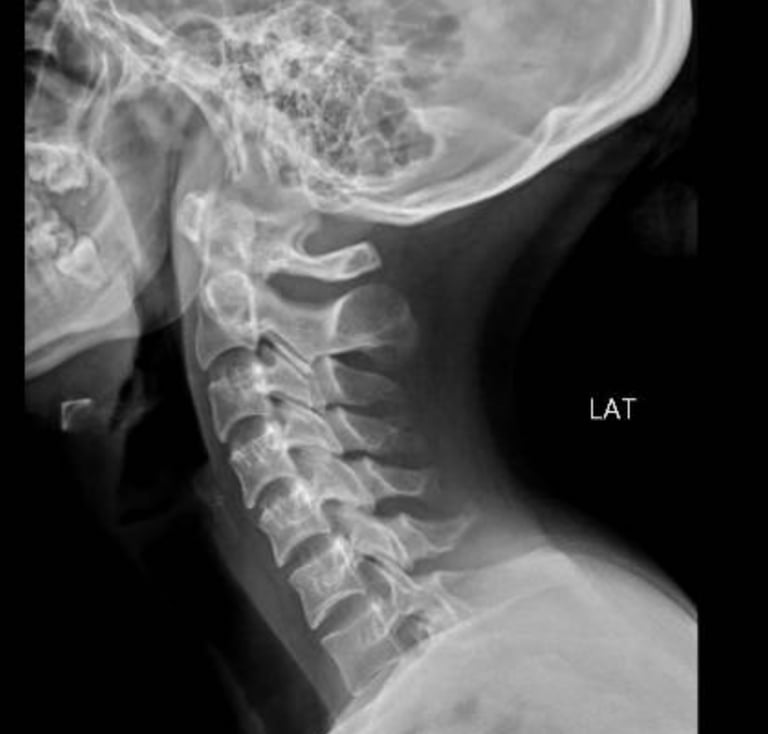

Columna cervical

Cervicalgia.

Hernias de disco intervertebral.

Fracturas vertebrales.

Luxaciones.

Radiculopatía cervical.

Mielopatía cervical.

Tumores de columna cervical.